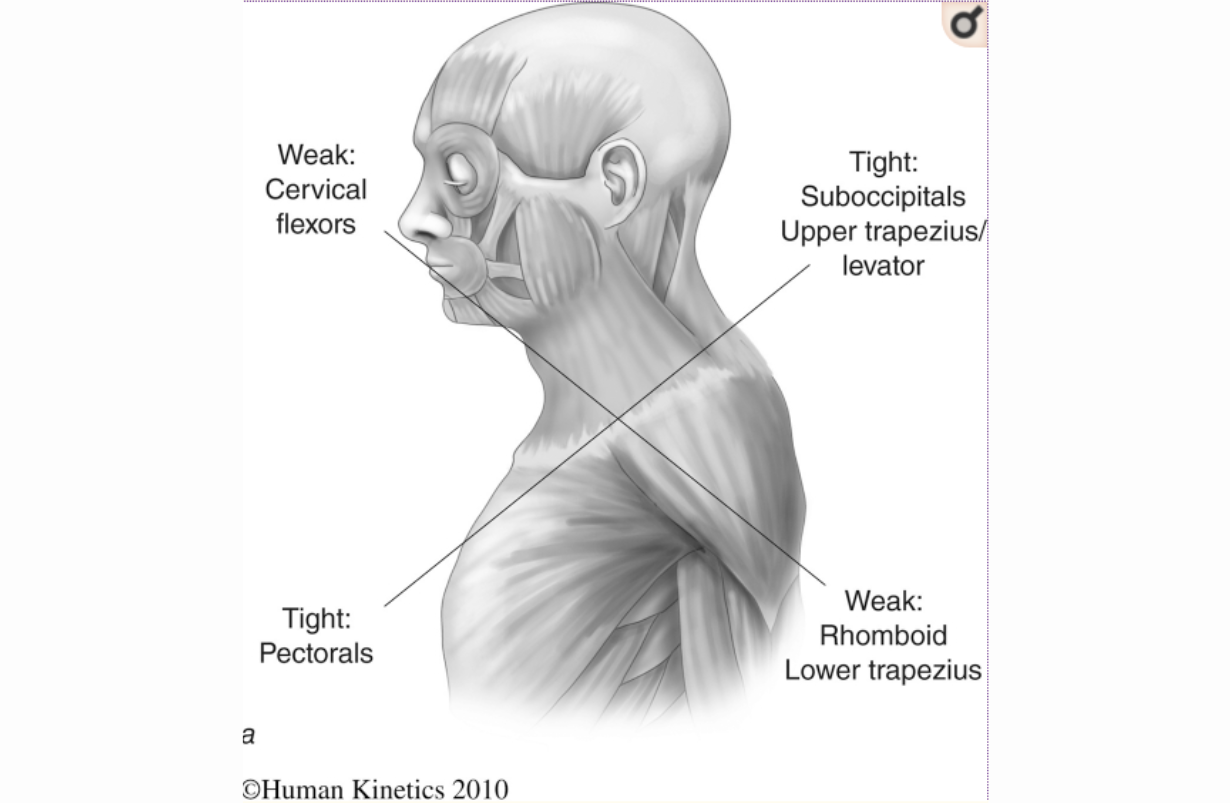

Thoracic Outlet Syndrome

Thoracic outlet syndrome occurs when nerves and/or blood vessels that serve the arm are compressed in the upper chest before entering the arm. The nervous elements, the brachial plexus, are the more common cause of arm and hand tingling, positionally related weakness, and pain; the vascular elements are subclavian and axillary. Usually the symptoms occur in certain positions, such as raising the arm overhead or depressing the shoulder. Medical treatment involves botulinum toxin to relax the scalenus muscles. BENEFICIAL POSES: Bharadvajasana II, Parighasana, Vrksasana, Garudasana,. EXPLANATION: The brachial plexus descends from the cervical spine between the scalenus anticus and medius muscles. Bharadvajasana II and Parighasana stretch these muscles, giving the nerves more slack to get out of harm's way between the clavicle and the coracoid process , two boney elements which they pass under as they enter and exit the thorax. Vriksasana and Garudasana aid in improving humeral control and scapular (shoulder blade) kinetics, both of which help people avoid the nerve compression that causes this syndrome. REFERENCE: Watson LA, Pizzari T, Balster S. Thoracic outlet syndrome part 2: conservative management of thoracic outlet.Man Ther. 2010 Aug;15(4):305-14. doi: 10.1016/j.math.2010.03.002. Epub 2010 Apr 9.